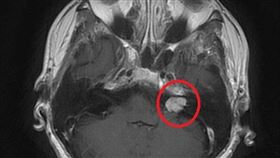

常聽見嗡嗡嗡、四肢麻刺感 竟是聽神經瘤

67歲的李先生兩年前開始有左耳聽力下降的情況,時常聽...

男頭暈聽力降 3公分聽神經瘤作怪

28歲黃姓男子半年前開始,每天起床後就感到莫名頭暈、...

單側聽力變差 竟是腦袋瓜出了問題

一位44歲的劉小姐左側聽力正常,但右側聽力從國中起就...